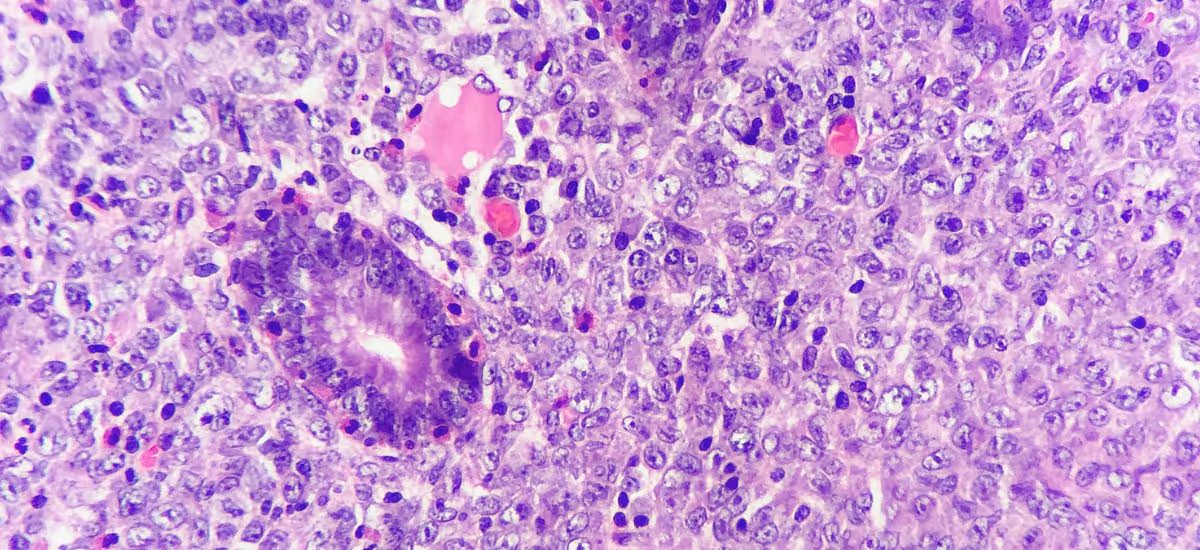

Lymphoma cells